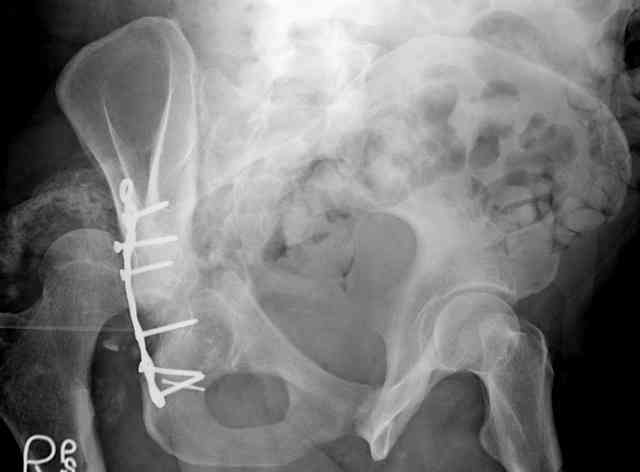

I'll include a few images of a similar injury in a similarly large male patient. This patient "showed up" in our ER c/o hip pain 2 months after being treated in the lateral position, without a quality reduction, without an anterior column transverse supporting implant, with an unbalanced plate applied too medially, with insufficient caudal segment fixation...it took over 8 hours and a 3+ l blood loss to debride the callus from front then

back, excise the HO, release his sciatic nerve, reduce the head-transverse-wall, and fix it...and now it's a staging procedure.

The 2nd example is of a motorcyclist with a transverse fracture-dislocation...he had a closed attempted reduction and placed in traction but the manipulative reduction was not concentric (not unusual for this injury pattern)...so the traction was adjusted to be just enough to disengage the head from the fracture (12#) until he could be cleared for surgery one day after injury...he was treated "urgently" then with a prone KL, clean the fracture, reduce and clamp it, screw it, support with a balanced plate, close, and enjoy...2-3hours, 400cc EBL, blah, blah, blah..